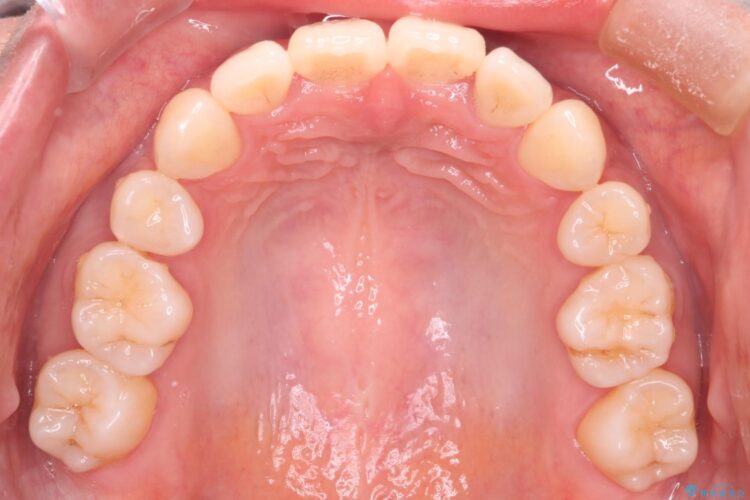

前歯のデコボコが改善され、噛みあわせも綺麗になりました。

歯肉退縮もなく、予定通りに治療を終えることができ大変ご満足いただけました。